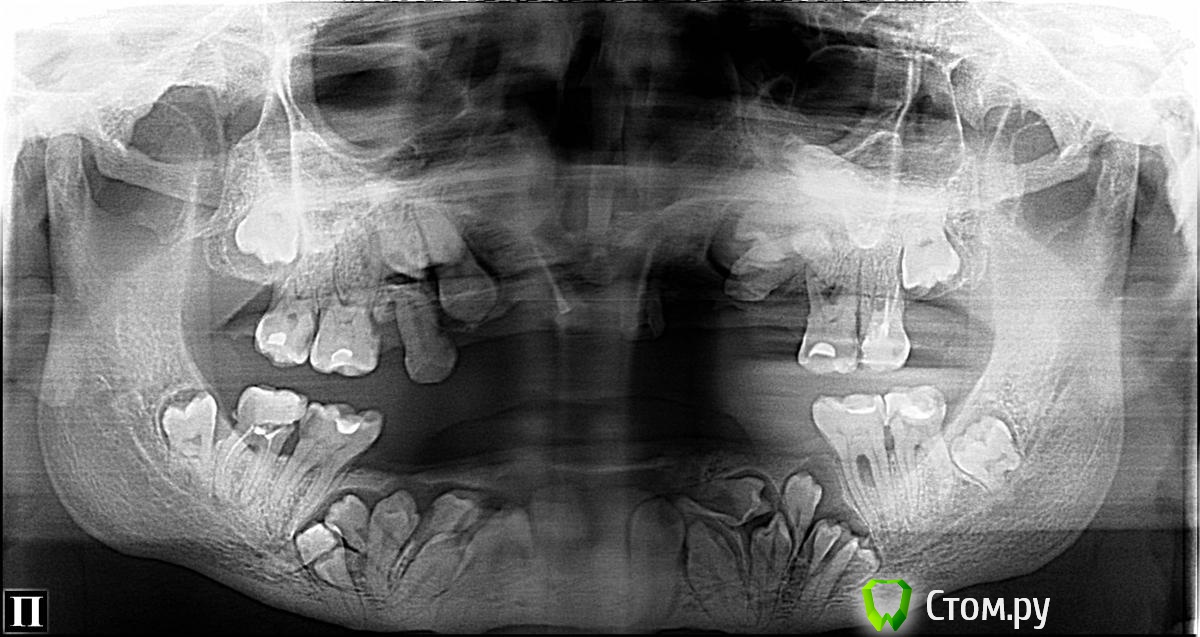

FBR Опубликовано 28 января, 2014 Поделиться Опубликовано 28 января, 2014 (изменено) Планируется протезирование на имплантатах ( в перспективе). Оперировать 1 этап (удаление зубов), планируем с ЛОРом. Изменено 28 января, 2014 пользователем FBR Ссылка на комментарий

FBR Опубликовано 29 января, 2014 Автор Поделиться Опубликовано 29 января, 2014 Красота. А сколько лет пациенту?34 года. Пока по плану с лором определяемся. Думаю убрать слева зубы с минимальной травмой кости. 25 лежит в носу и частично в кисте. Ссылка на комментарий

Al Kasandr Опубликовано 15 февраля, 2014 Поделиться Опубликовано 15 февраля, 2014 Достойный вызов!!!! работы на пару лет. Ссылка на комментарий

Bier Опубликовано 15 февраля, 2014 Поделиться Опубликовано 15 февраля, 2014 На мой взгляд на н.ч. необходима ортодонтия... Ссылка на комментарий